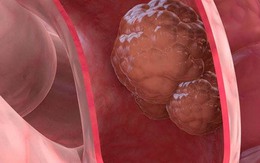

Ung thư trực tràng

Ung thư đại trực tràng là loại ung thư phổ biến thứ ba trên thế giới. Để phòng tránh và phát hiện sớm nó, đây là những việc bác sĩ không bao giờ làm.

Tỷ lệ mắc ung thư đại trực tràng ở người trẻ dưới 50 tuổi đang có xu hướng gia tăng nhanh chóng. Các nhà nghiên cứu cho rằng chế độ ăn uống kém lành mạnh là nguyên nhân chính của sự gia tăng này.

Theo các chuyên gia đến từ Viện Ung thư Dana-Farber ở Boston (Hoa Kỳ), ung thư đại trực tràng khởi phát sớm sẽ trở thành nguyên nhân chính gây tử vong do ung thư ở những người từ 20 tuổi vào năm 2030.

Ung thư đại trực tràng trước đây thường gặp ở người trên 50 tuổi, tuy nhiên tỉ lệ mắc ung thư đại trực tràng trong nhiều năm gần đây tăng nhanh ở giới trẻ.

Ung thư đại trực tràng thường gặp ở những người trên 50 tuổi, tuy nhiên tỉ lệ mắc ung thư đại trực tràng trong nhiều năm gần đây tăng nhanh ở giới trẻ. Điều đáng lo ngại là tỷ lệ ung thư này đã tăng lên tới 2% hàng năm ở những người trẻ tuổi.

Ung thư đại trực tràng là một trong những bệnh ung thư đường tiêu hóa phổ biến, thường gặp ở người trên 50 tuổi. Tuy nhiên, trong những năm trở lại đây, tỷ lệ mắc bệnh ở giới trẻ tăng nhanh đột biến. Theo thống kê, cứ 1/25 người có nguy cơ mắc ung thư đại tràng hoặc trực tràng tại Mỹ.